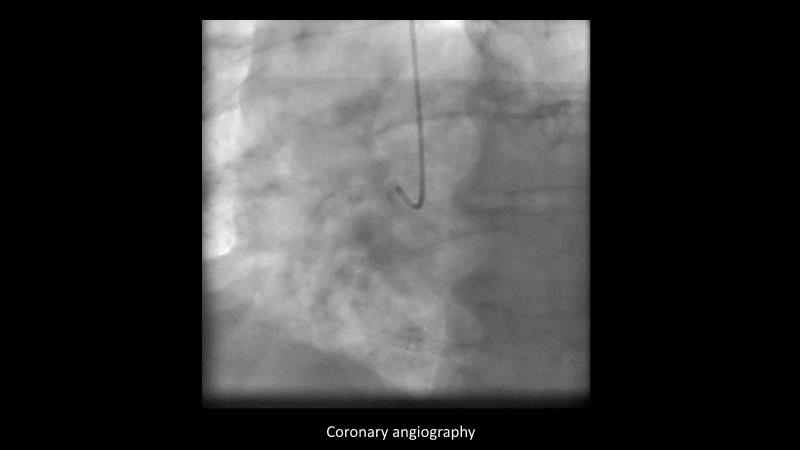

Making treatment and management of complex PCIs easier with Cre8 EVO

Maximize patient clinical outcomes in complex percutaneous coronary interventions (PCIs) by joining this session. Discover how accurate patient evaluation, advanced imaging/functional modalities, optimized procedures, and the Cre8 EVO device contribute to improved safety and efficacy, and review the challenges associated with DES implantation in complex PCIs.

- To find out how an accurate evaluation of patient profile, imaging/functional modalities, optimised interventional procedure and the proper selection of the device contribute to maximise patient clinical outcomes both in terms of safety and efficacy